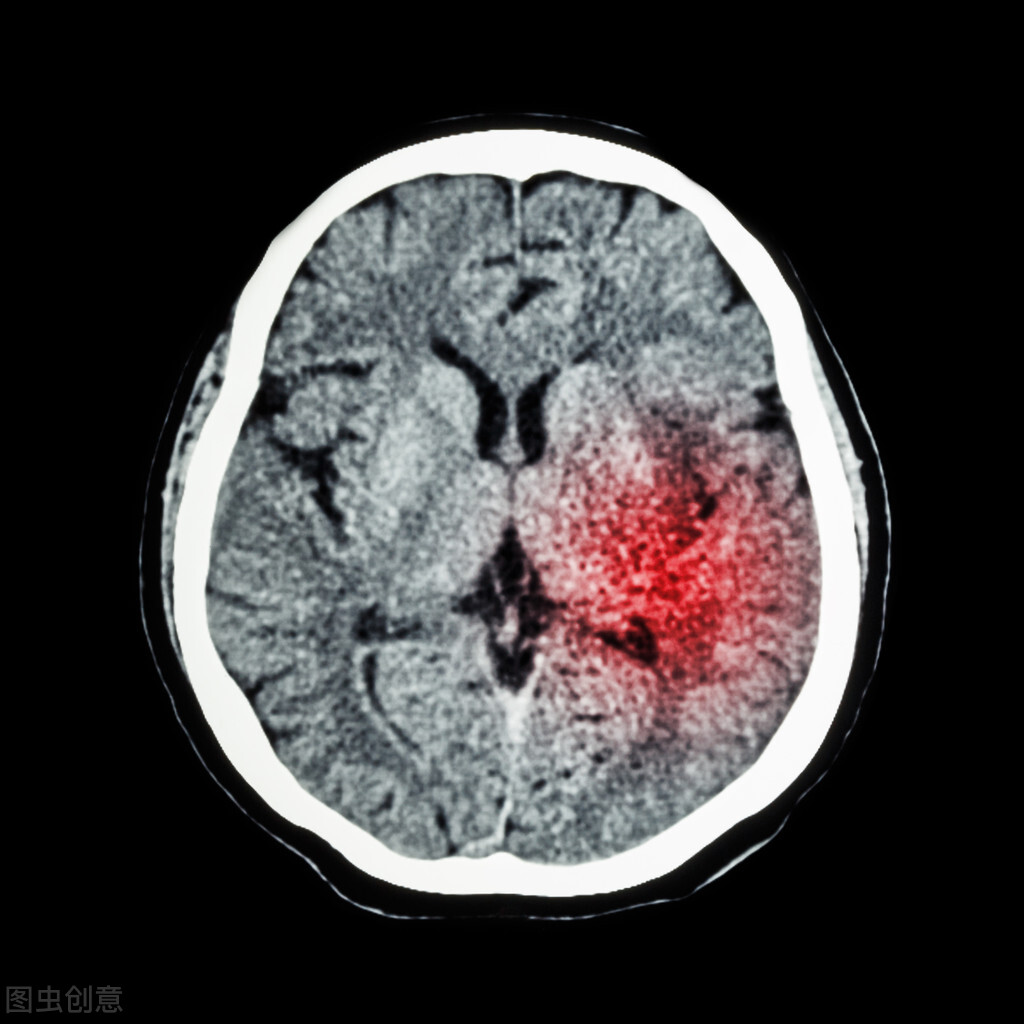

脑膜瘤是围绕大脑的组织的异常生长,称为脑膜。通常,脑膜瘤只需要医生定期检查和神经影像学检查,因为肿瘤生长非常缓慢。然而,有时肿瘤会压迫大脑或脊髓。在这种情况下,需要治疗。

手术切除脑膜瘤是大多数脑膜瘤病例的优选治疗方法。虽然我们的目标是切除所有的肿瘤,但这可能是不可能的,这取决于肿瘤的位置和大小。例如,如果肿瘤太靠近关键的大脑区域或血管,切除的危险可能会超过任何可预见的好处。例如,如果肿瘤位于大脑顶面或嗅沟,通常尝试完全切除。对于难以到达的区域,如斜坡,部分切除可能更合适。